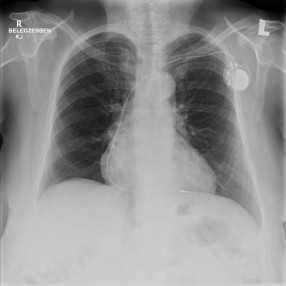

A Micra™ pacemaker mérete kevesebb mint egy tizede a hagyományos pacemakerekhez képest. Az eszköz teljes egészében a szívbe kerül beültetésre kiegészitő elektróda nélkül, így közvetlenül tudja segíteni annak szabályos működését. A készülék behelyezését röntgen átvilágítás alatt végzik, a beteg lágyéki vénáján keresztül bevezetett katéter segítségével. A megfelelő hely elérését követően a felvezető katéter eltávolításra kerül, és a 2 gramm tömegű szívritmushenger pedig a helyén marad.